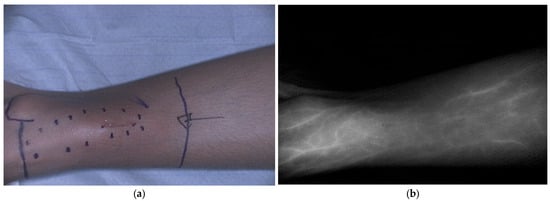

- Brookes, M.J.; Chan, C.D.; Crowley, T.P.; Ragbir, M.; Ghosh, K.M.; Beckingsale, T.; Rankin, K.S. Intraoperative Near-Infrared Fluorescence Guided Surgery Using Indocyanine Green (ICG) May Aid the Surgical Removal of Benign Bone and Soft Tissue Tumours. Surg. Oncol. 2024, 55, 102091. [Google Scholar] [CrossRef]

- Wang, H.; Ji, T.; Qu, H.; Yan, T.; Li, D.; Yang, R.; Tang, X.; Guo, W. Indocyanine Green Fluorescence Imaging May Detect Tumour Residuals during Surgery for Bone and Soft-Tissue Tumours. Bone Jt. J. 2023, 105-B, 551–558. [Google Scholar] [CrossRef] [PubMed]

| Clinical | Pediatric and young adults | Bone and soft tissue sarcoma | Guiding resection margins, identification of residual, and metastatic lesions | ICG 0.5–2.5 mg/kg 24 h before surgery | [36,37,38,39,40,41] | |